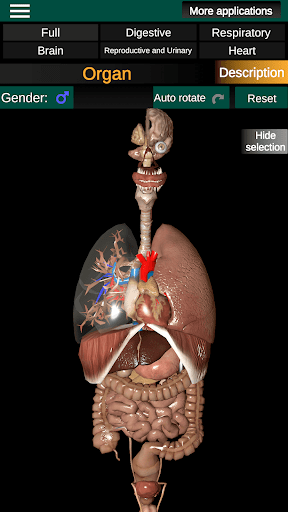

Показує 3D анатомічну модель основні органи людського тіла та опис кожного з них.

Що в додатку?

* Репродуктивна система, яка включає чоловічі та жіночі репродуктивні органи.

* Мозок, який включає головний мозок, мозочок і стовбур мозку.

* Легкий доступ і навігація (масштабування, 3D-обертання).

* Приховати або показати інформацію.

* Порівняйте чоловічі та жіночі органи.

* Описи кожного органу.